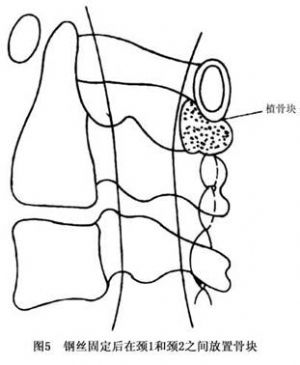

14.3.1 单纯性寰椎复位加内固定术

单纯性寰椎复位加内固定术即从后路暴露术野,将寰椎向后方牵出,并用中粗钢丝(最好是钛丝)将其固定至颈2及颈3的棘突上。以钢丝采取穿过棘突根部的方式更为理想,并酌情于颈1~2之间放置植骨块(图4,5)。但这种方法易失败,主要是因钢丝固定力度欠佳,且易断裂或引起骨折而失败。